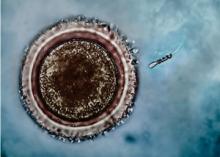

INFERTILITÉ: Aujourd'hui, pour rencontrer l'ovule, le spermatozoïde préfère être motorisé